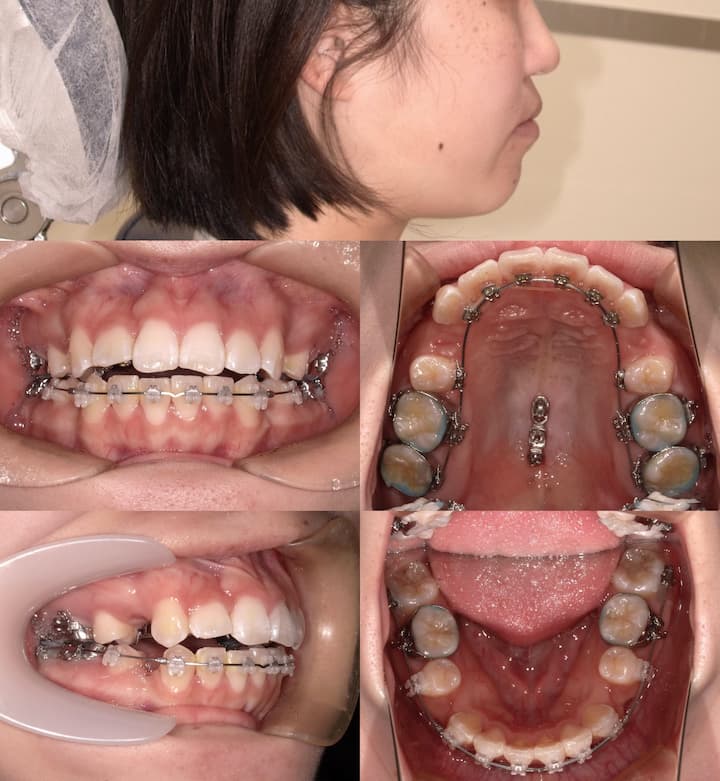

上顎大臼歯の圧下により下顎骨を反時計回りに回転させることで、オトガイ部の前方移動と下顔面高の減少を図り、口唇部の突出感を改善する計画としました。

咬合平面のコントロール

上顎大臼歯の圧下に際し、適切な咬合平面を維持するため、以下の対策を講じました。・フルサイズワイヤーの使用:.018×.025インチTMA(チタンモリブデン合金)ワイヤーを使用し、臼歯部のみが選択的に圧下するように設計

・パラタルバーの装着:上顎大臼歯の幅径を維持し、歯列弓形態の安定を確保

・前歯部の垂直的位置の維持:大臼歯圧下時に前歯部が挺出しないよう、ワイヤーで適切にコントロール

上顎大臼歯の圧下を伴う治療では、臼歯部にオープンバイト(開咬)を引き起こすリスクが存在します。特に、大臼歯のみが圧下され、前歯部が相対的に挺出してしまうと、前歯部での咬合接触が強くなり、臼歯部の咬合が失われる可能性があります。

本症例では、以下の対策を講じることで、このリスクを回避しました。

・フルサイズTMAワイヤーの使用:.018×.025インチのTMAワイヤーを使用することで、上顎歯列全体を一体として扱い、大臼歯のみが選択的に圧下するメカニクスを構築

・パラタルバーによる歯列弓形態の安定:左右大臼歯をパラタルバーで連結し、幅径の変化を防止

・前歯部の垂直的位置管理:ワイヤーにより前歯部の挺出を抑制し、適切な咬合平面を維持

・定期的な咬合状態の評価:治療過程における臼歯部の咬合接触を継続的に確認

これらの緻密な咬合管理により、臼歯部のオープンバイトを生じることなく、上顎大臼歯の圧下を達成することができました。